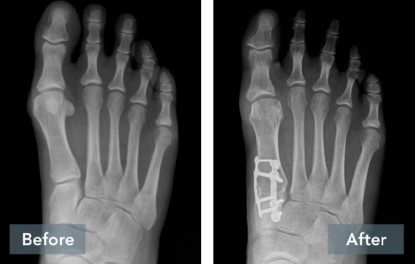

A common misconception is that a bunion is simply a “bump” that can be “shaved off.” But, bunions are more than a bump – they are complex 3D problems caused by an unstable joint in the middle of the foot. While the majority of bunion surgery is only 2D and fails to address the root cause, the Lapiplasty® Procedure provides a 3D correction and secures the unstable joint.

While traditional 2D osteotomy surgery cuts & shifts the bone to address the cosmetic bump, Lapiplasty® 3D Bunion Correction® does more – it corrects the entire bone in 3D and secures the unstable foundation to get you back on your feet typically within 3-1 0 days in a walking boot. The Lapiplasty® Procedure has also shown low recurrence; 97% and 99% maintain 3D correction in 13 and 17 months respectively.